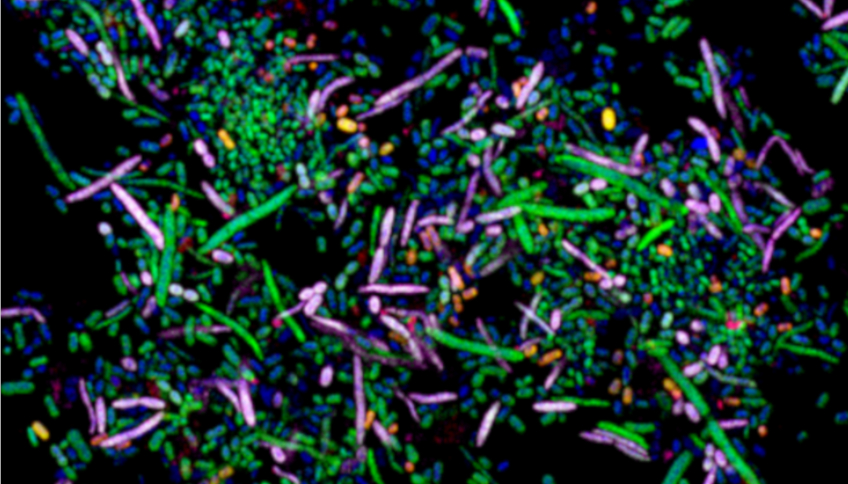

Zur Bestimmung der Mikroorganismen verwendeten die Forscher*innen schweres Wasser, das von den Mikroben gemeinsam mit den untersuchten Zuckern aufgenommen wird. Auf diese Weise markierte Organismen wurden dann mit Hilfe sogenannter Raman-Mikrospektroskopie in Verbindung mit Zellsortierung durch Optofluidik und mit Hilfe hochauflösender Massenspektrometrie aussortiert und untersucht. Das Forschungsteam konnte durch diese Methodik 51 unterschiedliche kommensale Mikroorganismen identifizieren, die dieselben Zucker der Darmschleimhaut verarbeiten wie Clostridioides difficile.